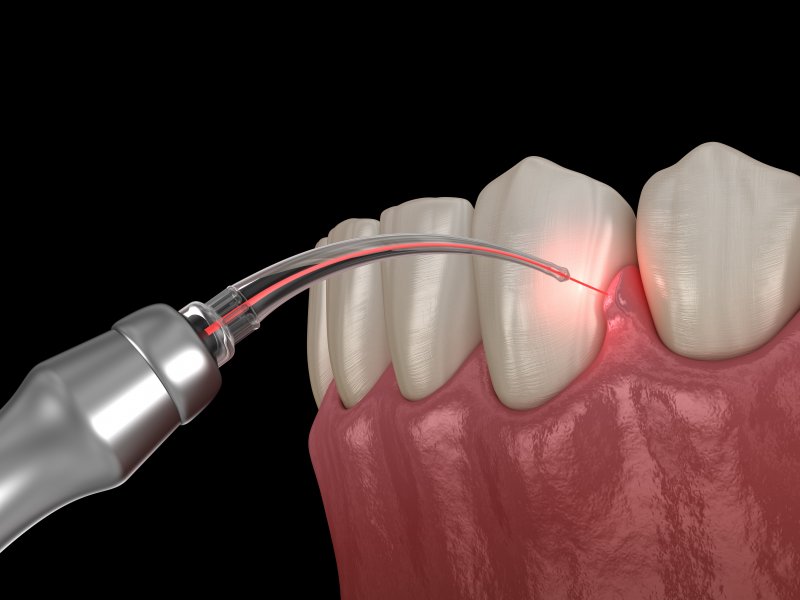

Laser Dentistry

Laser dentistry is kind and gentle. It’s pain free.

• Laser surgeries : No cut, No sew (stitches), No fear.

• Root Canal Treatment : To sterilize the infected root canal.

• Flap Surgery : Effective treatment for gum strengthening.

• Minimally invasive.

• Painless, bloodless, clean surgical field.

• Laser kills bacteria, risk of infection is reduced.

• Superior and faster healing.